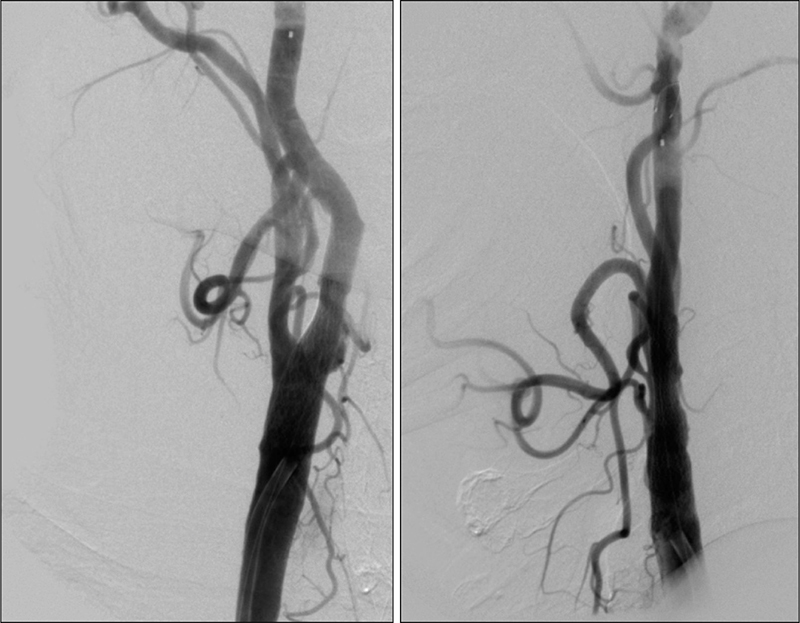

Εικόνα 3 και 4: Προσθιοπίσθια και πλάγια ενδοκράνια λήψη εγχύσεως στην αριστερή κοινή καρωτίδα. Υποτυπώδης ροή μόνο προς την αριστερή μέση εγκεφαλική (έμμεσο στοιχείο κινητοποιήσεως της παράπλευρης κυκλοφορίας από την αντίστοιχη πλευρά).

Εικόνα 5: Έγχυση στην δεξιά κοινή καρωτίδα. Εκτεταμένη αθηρωματική πλάκα του βολβού της δεξιάς έσω καρωτίδος, προκαλεί συγκεντρική στένωση 80-90%, χωρίς εξέλκωση.

Εικόνα 6: Προσθιοπίσθια ενδοκράνια λήψη εγχύσεως στην δεξιά κοινή καρωτίδα. Κίνητοποίηση της παράπλευρης κυκλοφορίας διά μέσου της προσθίας αναστομωτικής αρτηρίας με άρδρευση πλήρως της αριστερής πρόσθιας εγκεφαλικής και συμμετοχή στην άρδρευση της αριστερής μέσης εγκεφαλικής αρτηρίας.